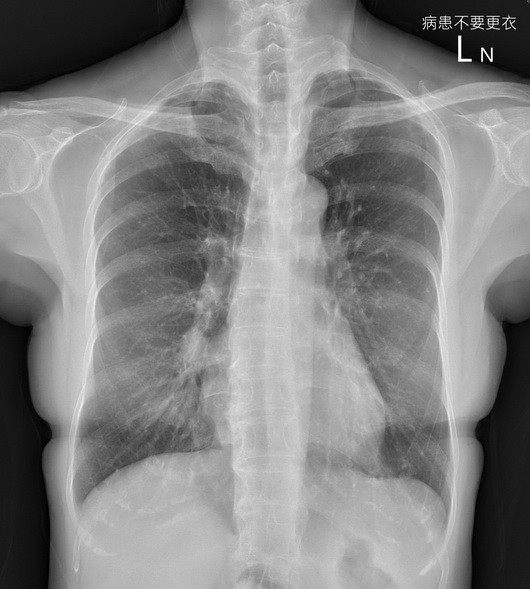

胸腔科接收一名60岁不抽烟女性患者,轻微的咳嗽半年多没好,结果进行计算机断层,发现是3公分的肺癌,大概第二期或三期。

主治医生说,患者期间去过其他医学中心,照X光看了没事,判断可能是长新冠,但治疗还是咳嗽没有好,后来来他的门诊。

医生指出,X光一照看完觉得有问题,“让大家找看看在哪里”;安排后续的计算机断层CT检查,发现是3公分的肺癌,大概第二期或三期。